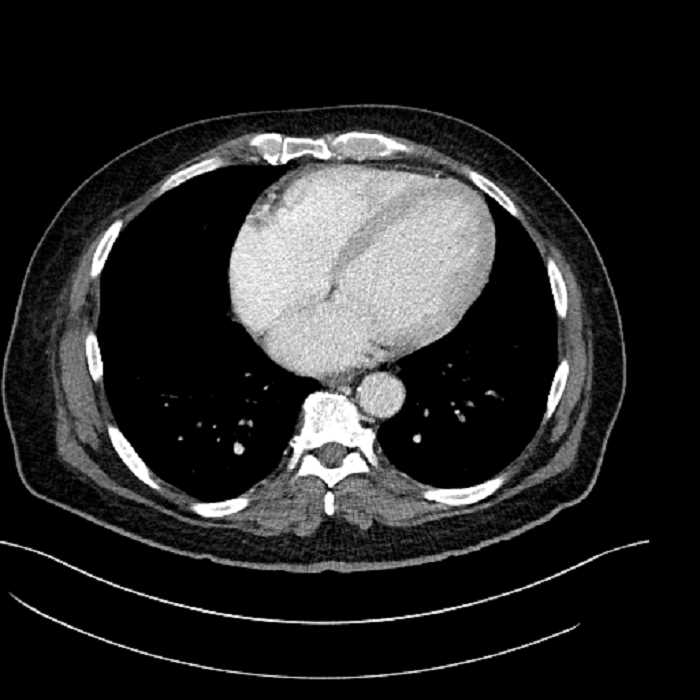

• Mild cardiomegaly

• Large fluid density structure in hepatic segments 7 and 8 measuring 10 x 7 x 7 cm with internal septation and circumferential ill-defined low density compatible with edema

• Peripherally enhancing subcapsular collections along the anterior margin of the left hepatic lobe measuring 3 x 1 cm and 2 x 1 cm

Acute sigmoid diverticulitis complicated by a small contained perforation and a large abscess in the right hepatic lobe. Additional small subcapsular abscesses along the anterior margin of the left hepatic lobe.

• The classic CT imaging appearance is a double target sign with internal low density surrounded by an internal enhancing rim (capsule) and a low density external rim (edema)

Hepatic abscess showing the double target sign with low density internally surrounded by a thin inner enhancing rim (red arrow) and ill-defined outer low density rim (yellow arrow). Blue arrow indicates an internal septation. Red arrows: additional smaller subcapsular abscesses. Red arrow: focal contained perforation associated with diverticulitis.